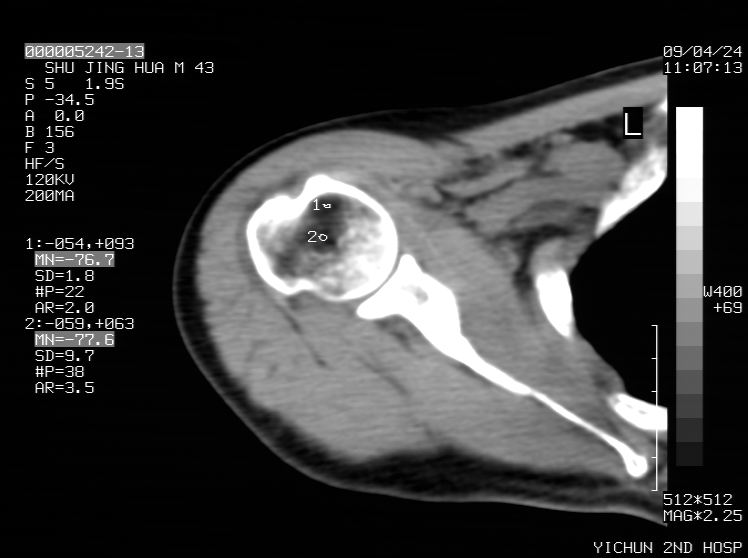

标题: CT19569:请会诊,女50岁,右肩疼痛数月 [打印本页]

标题: CT19569:请会诊,女50岁,右肩疼痛数月

考虑钙化性肩周炎,肱二头肌长腱或相应附属组织钙化

钙化性肌腱炎

是指钙盐沉积在变性肌腱中的一种无菌性炎症,常见于肩关节的肩袖肌腱,引起肩部疼痛和活动受限。分为急性和慢性两种类型,急性型有肩关节突然出现急性疼痛的发作史,夜间可痛醒。

以下是引用余辉在2009-4-24 15:24:00的发言:[br]考虑钙化性肩周炎,肱二头肌长腱或相应附属组织钙化

支持